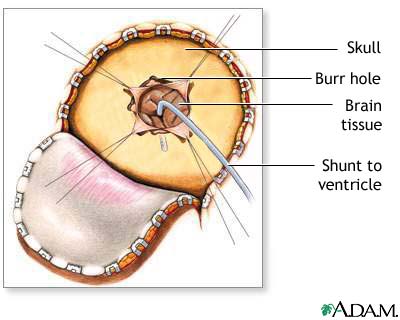

This procedure is done in the operating room under general anesthesia. It takes about 1 1/2 hours. A thin tube (catheter) is passed from the cavities of the head to the abdomen to drain the excess CSF. A pressure valve and an anti-siphon device ensure that just the right amount of fluid is drained.

The procedure is done as follows:

- An area of hair on the head is shaved. This may be behind the ear or on the top or back of the head.

- The surgeon makes a skin incision behind the ear. Another small surgical cut is made in the belly.

- A small hole is drilled in the skull. One end of the catheter is passed into a ventricle of the brain. This can be done with or without a computer as a guide. It can also be done with an endoscope that allows the surgeon to see inside the ventricle.

- A second catheter is placed under the skin behind the ear. It is sent down the neck and chest, and usually into the belly area. Sometimes, it stops at the chest area. In the belly, the catheter is often placed using an endoscope. The surgeon may also make a few more small cuts, for instance in the neck or near the collarbone, to help pass the catheter under the skin.

- A valve is placed underneath the skin, usually behind the ear. The valve is connected to both catheters. When extra pressure builds up around the brain, the valve opens, and excess fluid drains through the catheter into the belly or chest area. This helps lower intracranial pressure. A reservoir on the valve allows for priming (pumping) of the valve and for collecting the CSF if needed.